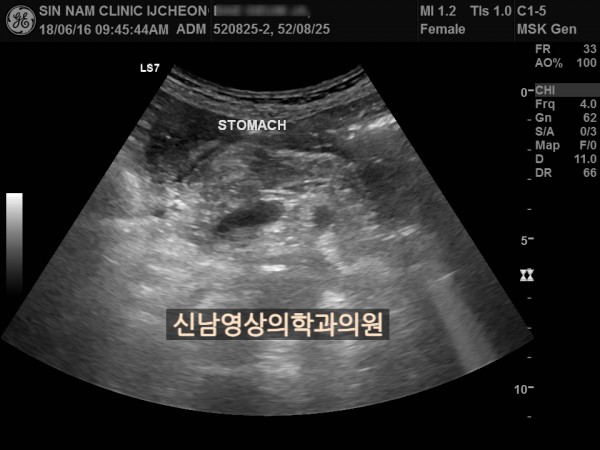

본 환자분은 변비가 지속되면서 좌하복부 통증이 있으셨던 분으로 본원에서 복부 초음파 검사를 진행하였습니다.

하행 결장 부위에서 장이 두꺼워진 소견이 보여 진행된 대장암의 가능성이 농후해보여 대학병원으로 전원해 대장내시경을 받고, 수술로 2기암으로 진단되신 케이스입니다.